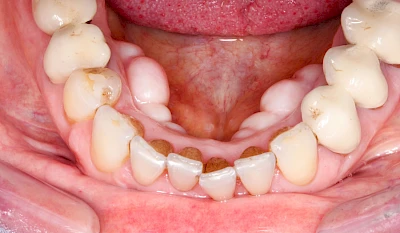

Knochenschwund (Atrophie)

Gehen die Zähne verloren, baut häufig auch der Kieferknochen ab (Knochenschwund). Die Geschwindigkeit und das Ausmaß des Knochenschwundes ist von vielen Faktoren abhängig. Neben der genetischen Veranlagung spielen auch Überbelastungen in Folge, z. B. bei ständigem Knirschen oder Pressen, eine Rolle. Auch wenn Zahnprothesen Tag und Nacht getragen werden, kann die ständige Belastung der Schleimhäute und des Knochens den Knochenschwund beschleunigen.

In seltenen Fällen schwindet nur der Knochen, aber nicht die bedeckenden Schleimhäute. In diesen Fällen spricht man von einem sogenannten "Schlotterkamm".